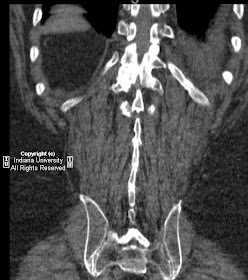

Findings

Pseudo-articulation and close approximation of multiple hypertrophic lumbar spinous processes. Associated sclerosis and degenerative spurring. Vertebral compression deformities and vaccuum disks with prior L1 and L4 vertebroplasty.

Diagnosis: Baastrup’s disease

Hypertrophy of spinous processes of adjacent vertebral bodies in close approximation or actual contact; i.e., arthritic joints between the spinous processes.

Joints undergo reactive sclerosis/degenerative change, including formation of degenerative cysts as seen in this case.